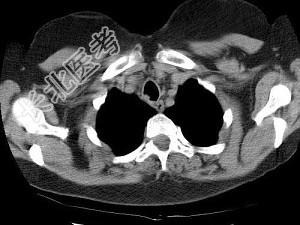

- 单项选择题男,68岁, 呼吸困难、轻度吞咽困难3月余,结合CT图像, 最可能的诊断是 ( )

A、气管乳头状瘤

B、气管脓肿

C、气管炎性假瘤

D、食管癌

E、甲状腺癌